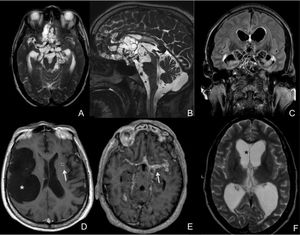

MRI of extraparenchymal neurocysticercosis

CT와 MRI는 병변의 수, 양상, 치유 단계, 면역계의 기생충 반응에 대한 객관적인 정보를 제공한다.[7] MRI는 다양한 각도에서 평가가 가능하고 선명한 영상을 제공하여 CT 스캔에서 놓칠 수 있는 뇌 뒤쪽이나 두개골 근처의 작은 병변을 식별하는 데 유용하다. CT는 뇌의 석회화를 감지하는 능력이 뛰어나 뇌의 칼슘 축적을 확인하는 데 더 민감하다.[2]

살아있는 소포성 낭종은 작고 둥근 병변으로, 주변 부기가 거의 없고 조영제가 필요하지 않다. 촌충 머리(스콜렉스)는 보통 낭종 내부에 비대칭적인 결절로 나타나며, 이러한 머리를 가진 여러 개의 살아있는 낭종은 진단을 뒷받침한다. 낭종이 파괴되기 시작하면(콜로이드 낭종) 경계가 불분명해지고 부기로 둘러싸이며, 링 또는 결절성 조영 증강을 보인다. 석회화된 유구낭미충은 CT 스캔에서 부기 없이 조영되지 않는 고밀도 결절로 나타난다.[8]

신경낭미충증의 영상, 병리, 수술 소견